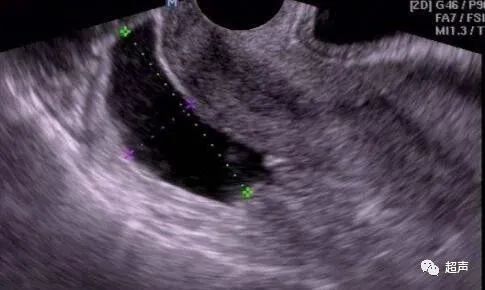

女性腹腔的末点是“直肠子宫陷凹”,是在直肠和子宫之间形成的腹膜凹陷。

盆腹腔因为生理性或病理性原因产生的液体会集聚到这个低点,而这个“窝”的容量非常小,只要有少量的液体,B超就可以在子宫直肠窝检测到有积液,并报告“盆腔积液”。

如无法排除病理性盆腔积液可能,临床医生会建议行妇科检查、血常规、B超、阴道后窟窿穿刺等检查以查明病因,再做进一步治疗。

▲阴道后窟窿